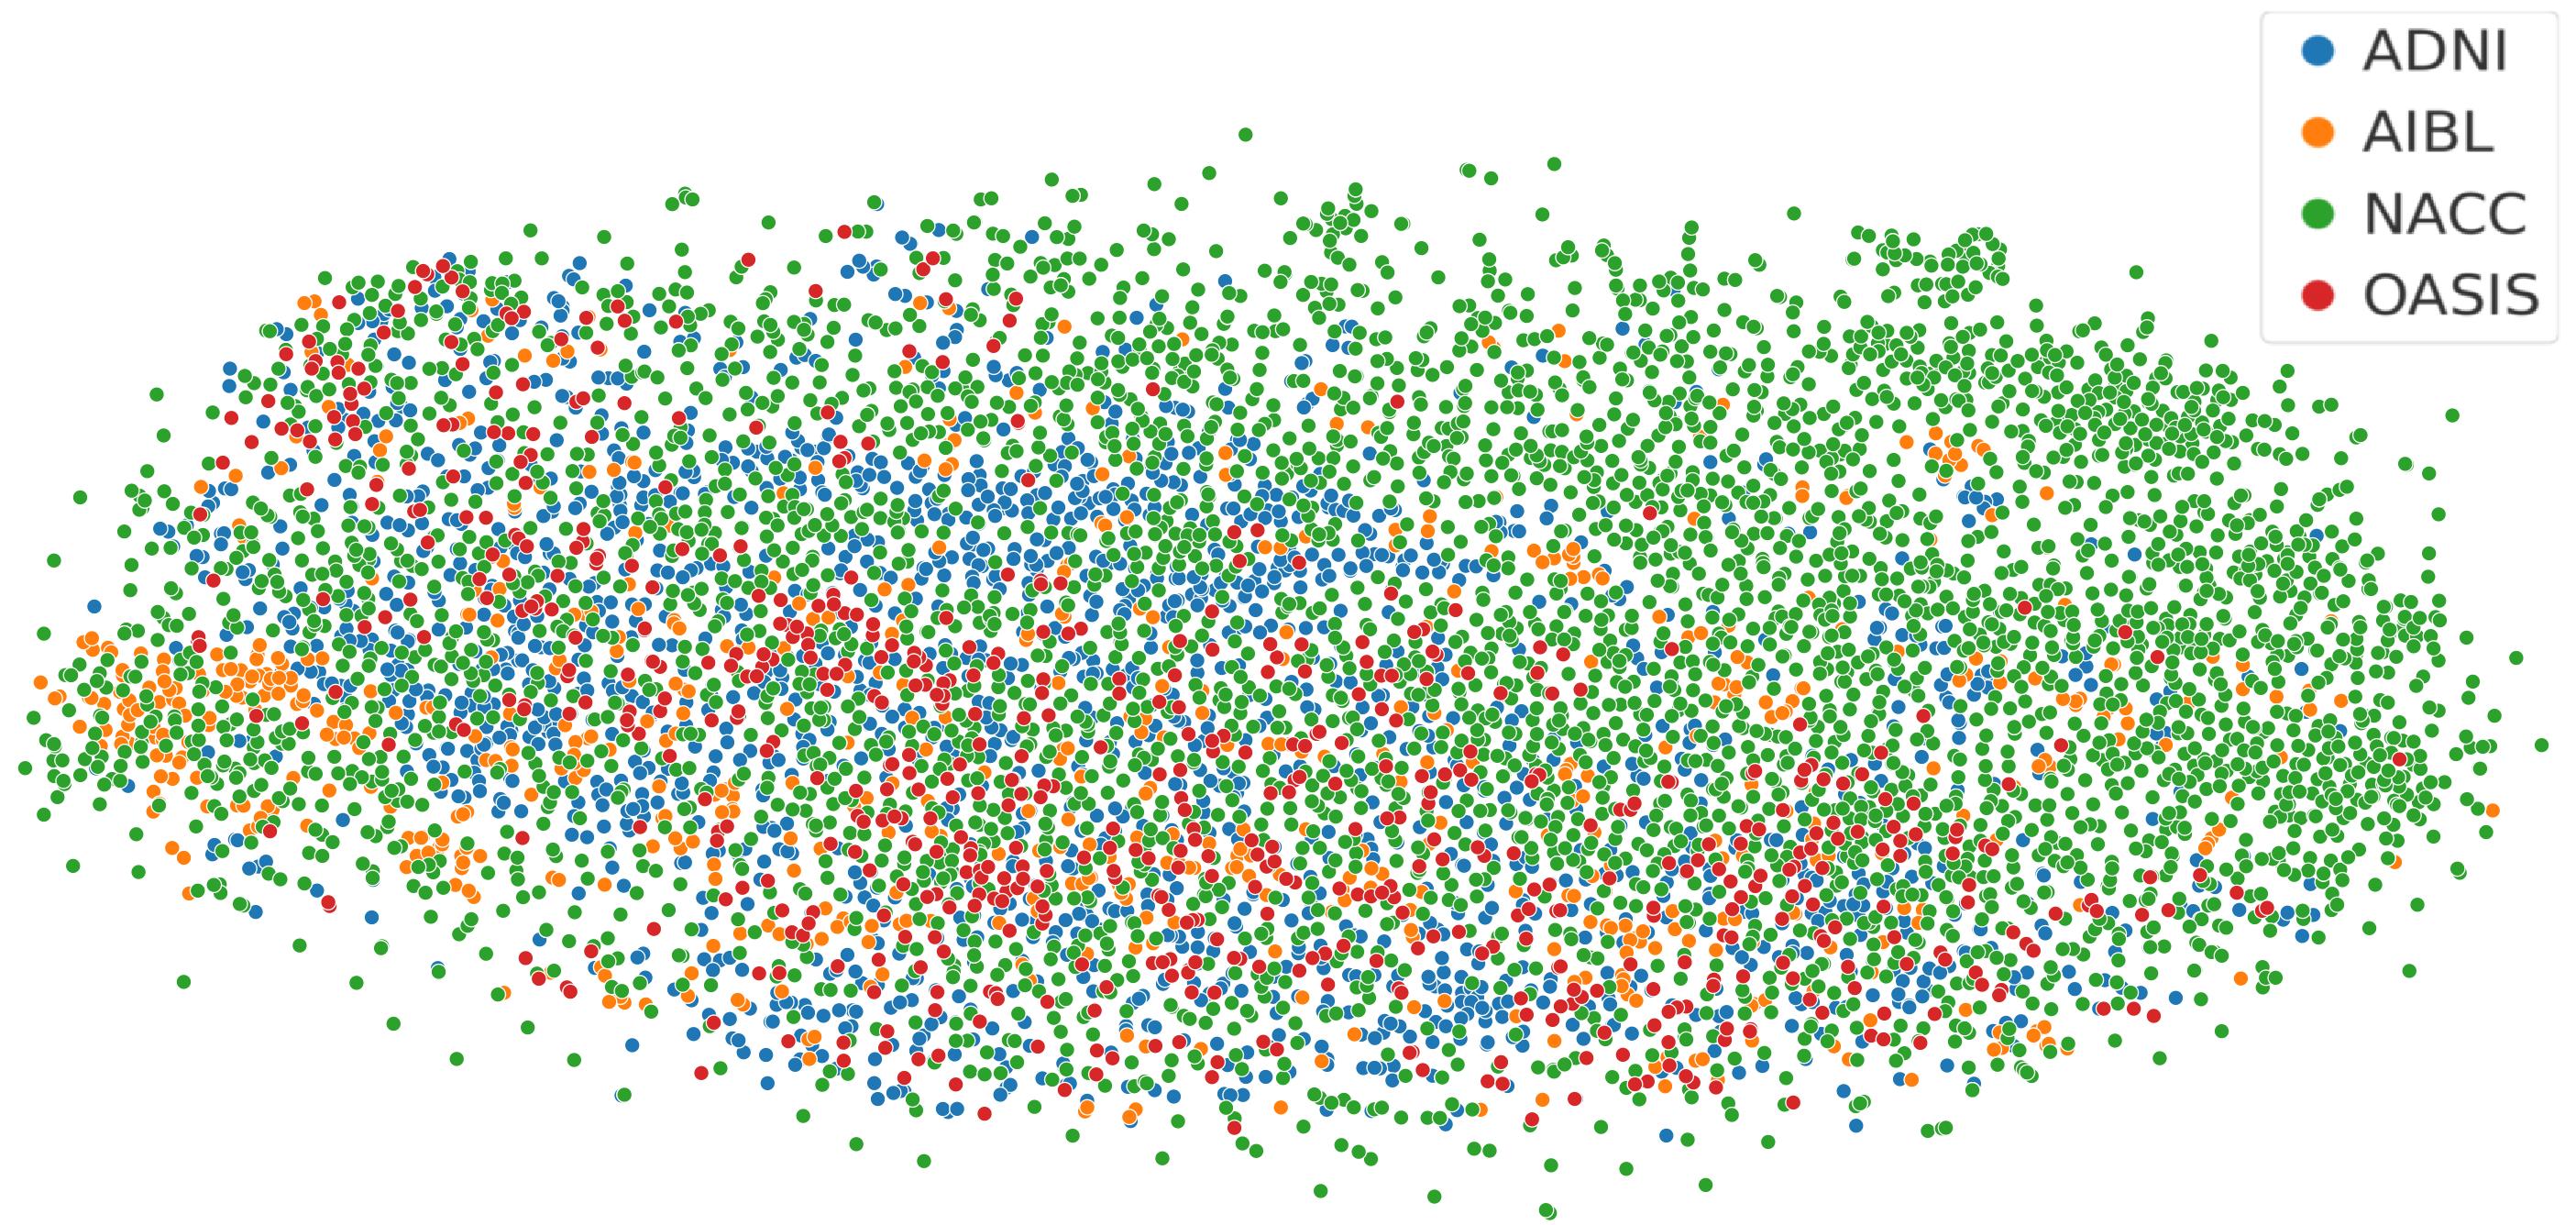

All sMRI volumes were preprocessed using a standardized pipeline adapted from [50]. The scans were first reoriented to match the MNI space. Brain extraction was performed using the FSL BET tool [51], generating a mask that preserved gray matter, white matter, cerebrospinal fluid, and subcortical regions, while excluding extracranial tissue, brain stem and cerebellum. Following skull stripping, a two-stage linear registration was applied: an initial affine alignment to the MNI-152 coordinate system, followed by repeated skull stripping and registration to refine alignment and remove residual non-brain voxels. Intensity inhomogeneities were then corrected using N4 bias field correction to reduce artifacts and enhance inter-subject consistency. Despite uniform preprocessing across datasets, inter-dataset differences were observed, likely arising from variations in scanners, imaging protocols, and participant demographics. These differences are reflected in the t-SNE embeddings from the ablation study (see Fig. 4a, cf. Section 4.4), where representations obtained from the 3D U-Net exhibit dataset-specific clustering patterns, thus making the datasets a strong testbed for SDG.

Figure 4: t-SNE visualizations of sMRI embeddings under different training settings. Data were drawn from four cohorts: NACC, ADNI, AIBL, and OASIS. The vanilla 3D U-Net (a) shows clear cohort-specific clustering, with AIBL forming compact islands and OASIS concentrated in the upper region, while ADNI and NACC remain distinct. EFDM (b) increases inter-cohort mixing, creating a dense shared embedding space though NACC still trends toward the outer edge. EM1 (c) and EM2 (d) further enhance overlap, dispersing cohort-specific clusters and producing a more uniform interleaved structure.

Lastly, across the t-SNE embeddings in Fig. 4, the vanilla 3D U-Net in Fig. 4a showed the clearest separation between cohorts, with AIBL forming several islands and OASIS concentrated in the upper region. EFDM in Fig. 4b produced slightly better inter-cohort mixing, although NACC showed clustering toward the outer edge. EM1 in Fig. 4c further dispersed cohort-specific islands, distributing AIBL and OASIS more uniformly and increasing overlap throughout the embedding without obvious isolated clusters. EM2 in Fig. 4d shows a similar degree of mixing to EM1, with a slightly tighter interleaved core and only a few outer zones dominated by NACC. Overall, the progression from baseline to EFDM and then to EM1/EM2 illustrates a shift from dataset-driven clustering toward reduced cohort bias.